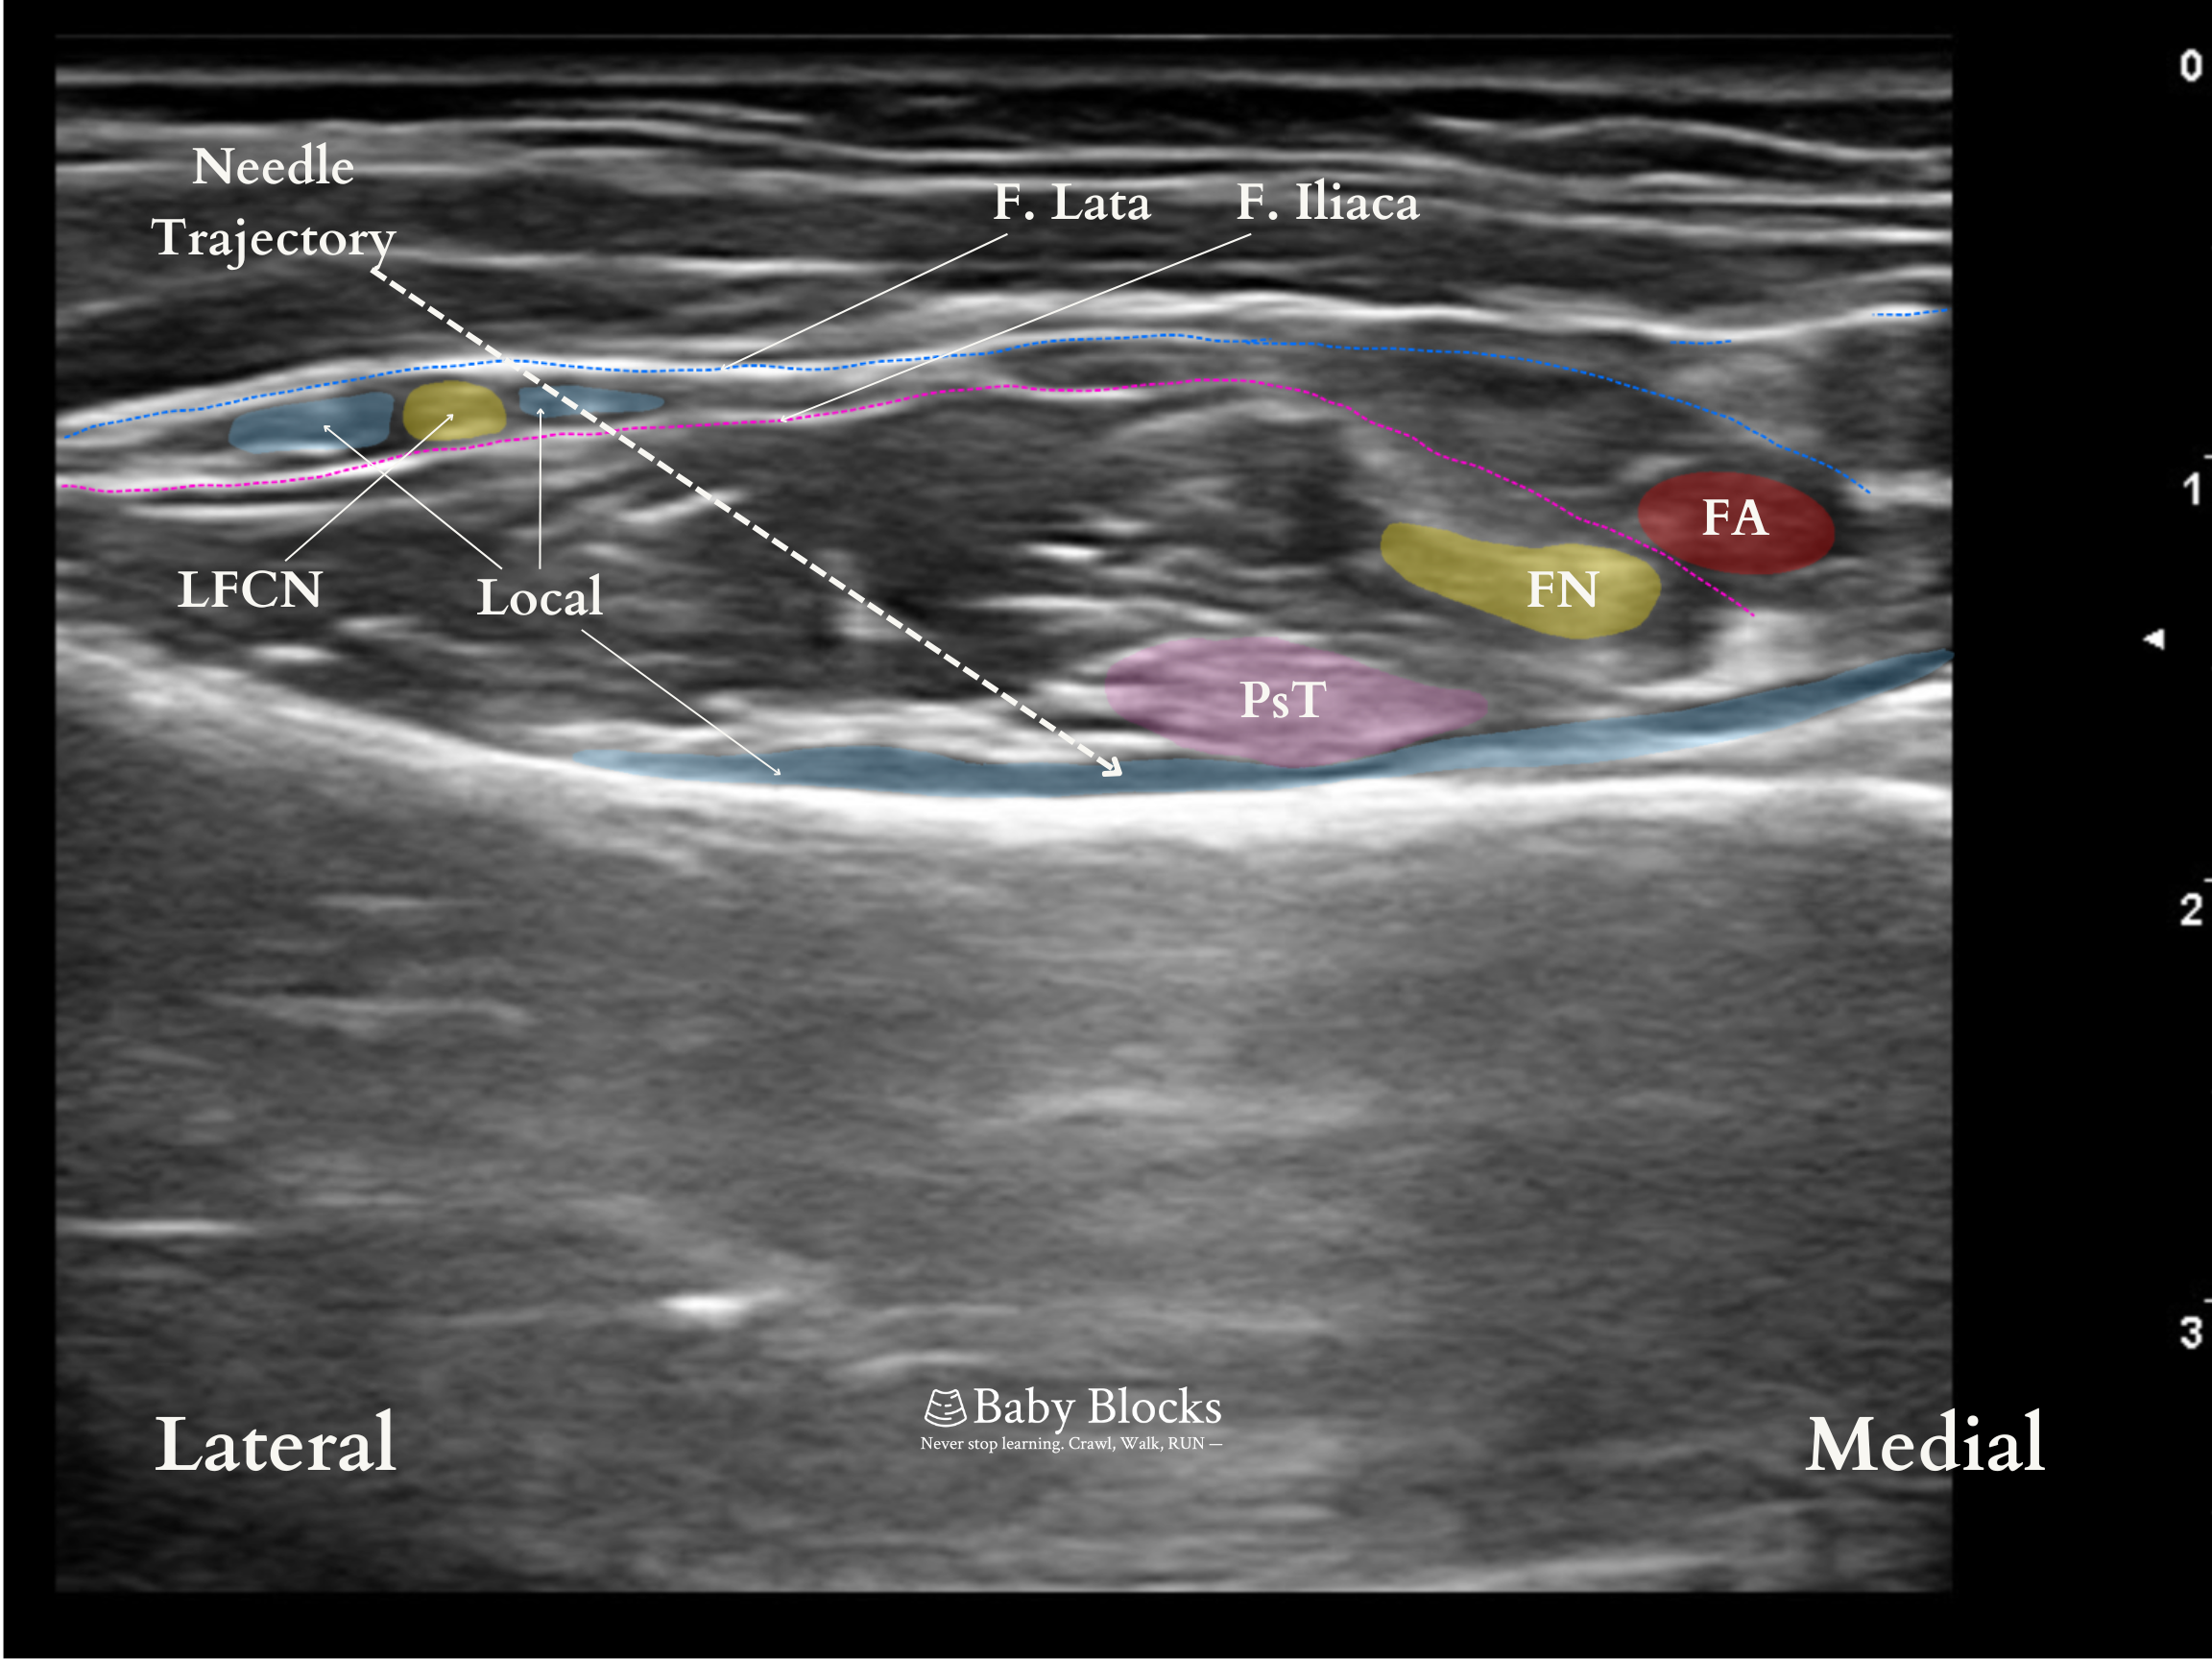

A linear ultrasound probe is positioned above the AIIS and rotated about 45 degrees in the direction of the pubic ramus. The femoral artery, pectineus muscle, and iliopsoas muscle and the psoas tendon are visualized.

A slight caudal tilt can be beneficial both for creating a better distance between the psoas tendon and femoral artery and nerve; and also for distribution of local anesthetic more caudally and directly to the sensory branches.

The needle is advanced from the lateral to the medial region using the in-plane approach. The area for the injection is between the pubic ramus and the psoas tendon. The local anesthetic is administered gradually once the fascia under the psoas tendon has been crossed and a negative aspiration test has been completed.

Linear spread above pubic ramus. The psoas tendon should be pushed up during injection.

Coverage: Anterior hip capsule. The lateral thigh requires separate lateral femoral cutaneous coverage. A fascia iliaca block may be required if blockade of both the femoral and lateral femoral cutaneous nerves (LFCN) is desired. A small space on the medial thigh, just above the knee, requires obturator nerve coverage.

The LFCN could be seen in the same view. While removing the needle, it can be blocked without requiring another puncture after completing the PENG block.